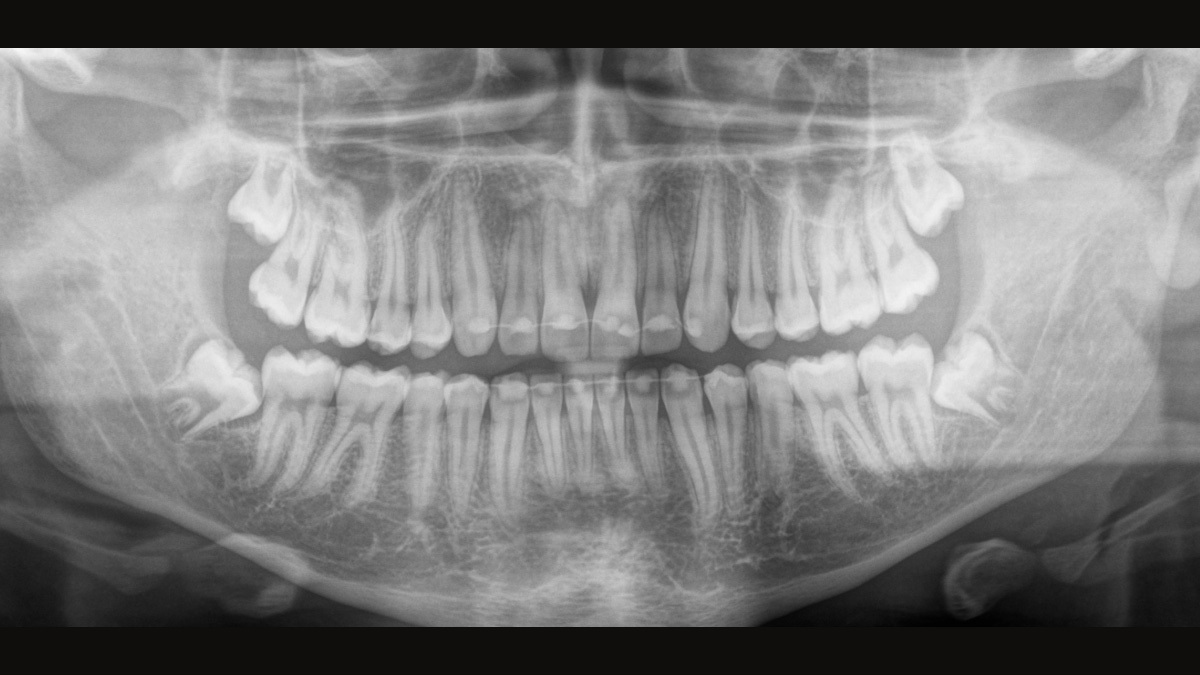

ダイレクト コンバージョン センサー(DCS) 画像診断を次のステージへ

ダイレクト コンバージョン センサー(DCS)によりパノラマ撮影品質を次のステージへ レントゲン画像は直接電気信号に変換されます。そのため、従来のシステムの場合のように、光信号への変換によるデータロスがなく、その結果、低い放射線量でも、非常に鮮明さと高いコントラストを備えた画像が得られます。適切な治療を支援するための正確な診断が可能になります。

サンプル画像は、DCSテクノロジーを使用していない場合と使用した場合のパノラマ画像です。矢印を使用してコントロールを画像上でドラッグすると、DCSセンサーが画質の質と診断の可能性に与える違いを確認できます。